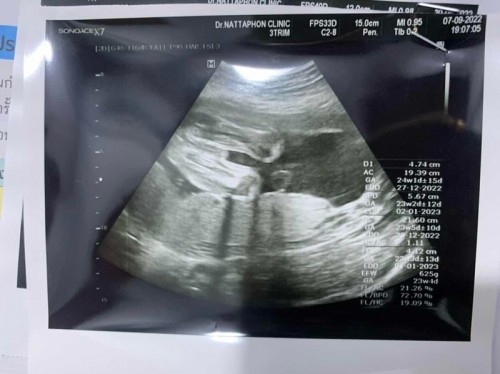

คุณหมอทักว่าจู๋หนูจิ้มลิ้มมาก

ปรบมือให้หมอก่แนเลยค่ะ. หมอดูออกได้ไง. เราพยายามดูแทบตาย ดูไงก็ไม่เห็นอะไรเลย ขนาดซาวตอน 7 เดือน เห็นหัว แขนขา. มองไม่ออกจริวๆ เรื่อวเพศ